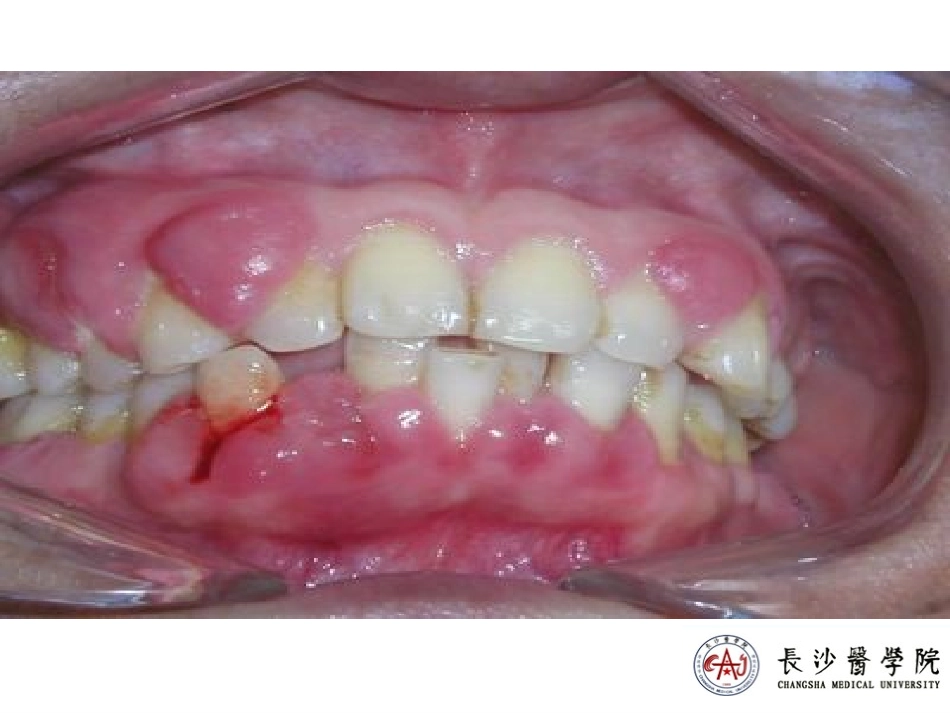

2024年10月20日星期日临床表现、基本病理变化、发生发展过程clinicalfeatures、histopathologicfeatures、stages12级本科口腔三班【clinicalfeatures】Ⅰ.发病情况:慢性牙周炎是最常见的口腔疾病之一,中老年发病率高,严重影响口腔健康,是口腔医学中最主要研究对象之一。Ⅱ.症状体征:主要表现为牙周溢脓和牙齿松动。可有咀嚼无力、牙龈肿胀、出血牙周袋溢脓牙齿松动、移位直至脱落。Ⅲ.X线:主要表现为牙槽嵴顶消失,牙槽骨硬骨板吸收,牙周膜间隙增宽。【histopathologicfeatures】1.活动期牙周炎的病理变化2.静止期牙周炎的病理变化3.牙槽骨吸收与牙周袋形成在临床病理上可分为三种情况1.活动期牙周炎的病理变化①牙面有菌斑、软垢及牙石②牙周袋内大量炎症渗出物1.活动期牙周炎的病理变化③沟内上皮出现糜烂/溃疡,一部分上皮向结缔组织内增生呈条索状/鱼眼状,有大量炎症细胞浸润。④结合上皮向根方增殖/延生,形成深的牙周带,其周围有密集的炎症细胞浸润。⑤沟内上皮和结合上皮下方的胶原纤维水肿/变性/丧失,大部分被炎症细胞取代,牙槽嵴顶骨吸收明显。1.活动期牙周炎的病理变化⑥牙槽骨出现活跃的破骨细胞性骨吸收陷窝。牙槽嵴顶及固有牙槽骨吸收破坏。1.活动期牙周炎的病理变化⑦牙周膜的基质及胶原变性、降解,由于骨的吸收、破坏,导致牙周膜的间隙增宽。⑧深牙周袋致使根面的牙骨质暴露,可见牙石与牙骨质牢固的附着。1.活动期牙周炎的病理变化【histopathologicfeatures】1.活动期牙周炎的病理变化2.静止期牙周炎的病理变化3.牙槽骨吸收与牙周袋形成在临床病理上可分为三种情况①沟内或袋壁上皮及结合上皮周围炎症明显减少,在牙周袋与牙槽骨之间可见大量新生的纤维结缔组织,或见粗大的胶原纤维束增生,其间可见少量的慢性炎症细胞浸润,还可见新生的毛细血管。②牙槽骨的吸收呈静止态,一般看不到破骨细胞。常可见原有的吸收陷窝区有新的类骨质形成。牙槽嵴部位的吸收亦可见类骨质或新生骨的形成。③牙根面被吸收的牙骨质也出现新生的现象。增生的粗大胶原纤维束附着在根面的牙骨质上,常呈棘状增生象,被吸收的牙骨质也见类骨质或新形成的牙骨质。【histopathologicfeatures】1.活动期牙周炎的病理变化2.静止期牙周炎的病理变化3.牙槽骨吸收与牙周袋形成在临床病理上可分为三种情况3.牙槽骨吸收与牙周袋形成在临床病理上可分为三种情况1.龈袋(gingivalpocket)又称假性牙周袋。是牙槽骨尚无明显的吸收,牙槽骨高度并未丧失,仅仅是牙龈组织由于炎症性增生、肿大,导致龈缘覆盖牙冠面形成的龈袋。3.牙槽骨吸收与牙周袋形成在临床病理上可分为三种情况2.骨上袋(supragingivalpocket)牙周袋底在牙槽嵴顶的上方,由于牙槽嵴为水平型骨吸收,其高度明显降低,导致骨上带形成。3.牙槽骨吸收与牙周袋形成在临床病理上可分为三种情况3.骨内袋(intrabonypocket)牙周袋底在牙槽嵴顶的下方,牙槽骨在袋的侧方,牙周袋处于牙根面与牙槽骨之间,主要由于牙槽嵴为垂直型骨吸收所致。牙槽骨吸收与牙周袋的关系【stages】掌握1.从组织病理学的角度解释慢性牙周炎的临床症状牙周袋形成:牙周组织炎症导致的牙周组织破坏,结合上皮与牙体剥离并且向根方增殖。牙槽骨吸收:多种致炎因子的作用下,导致破骨细胞活跃,吸收牙槽骨。牙周溢脓:牙周袋的化脓性炎症。牙松动:牙周组织的炎症性破坏,合并的咬合创伤等使牙周膜纤维破坏,产生牙松动。2.慢性牙周炎的基本病理变化是什么?牙周袋形成和牙槽骨吸收。3.从组织病理学的角度叙述慢性牙周炎的发生发展过程。慢性牙周炎形成的4个期:始发期、早期病变、病损确立期、进展期及其病理变化。